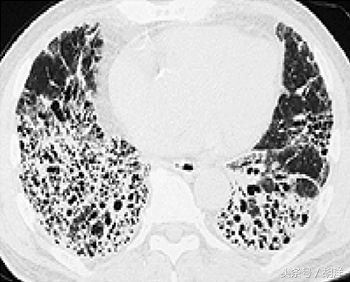

5.间质性肺炎 对于中国病人口服靶向药物后发生间质性肺炎的几率比较低,大概0.5-1%,出现胸闷,气喘加重时建议复查胸部CT,明确是否出现间质性肺炎,及时激素治疗,严重间质性肺炎病人需要停止用药。